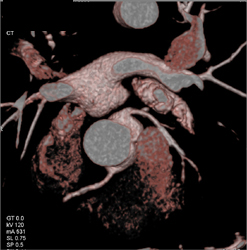

Diagnosis

Patent LAD Stent